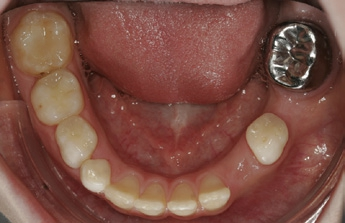

Eine weitere Restaurationsform steht zwischen den direkten und indirekten Restaurationen: Die zur Versorgung von Milchmolaren üblichen präformierten Stahlkronen wurden in klinischen Studien auch zur Versorgung von bleibenden MIH-Molaren erfolgreich angewandt (Abb. 4). Die Überlebensraten dieser Restaurationsform scheinen hoch zu sein (95 % nach 3 Jahren). Bei stark zerstörten MIH-Zähnen könnte diese Restaurationsform zudem mit minimaler Präparation im Sinne einer Hall-Krone angewendet werden, was gerade vor dem Hintergrund der hohen Empfindlichkeit der Zähne relevant sein dürfte [28,36,53]. Die Ästhetik dieser Restaurationsform ist jedoch eingeschränkt und die langfristige Abrasionsstabilität der relativ weichen Legierungen bisher nicht belegt. Zukünftig könnten präformierte Zirkonoxidkronen eine Alternative darstellen.

Dieses Stufenkonzept sollte geleitet werden von dem Gedanken, zunächst wenig invasive Therapien einzusetzen und nur schrittweise eskalierend zu therapieren. Eine Ausnahme stellt – wie dargelegt – die frühe Indikationsstellung zur Extraktion der MIH-Molaren dar; hier muss mitunter (gerade zur temporären Versorgung der Zähne) invasiver vorgegangen werden. In der Regel ist zur Restauration von MIH-Defekten im Molarenbereich Komposit empfehlenswert. Auch die Nutzung von präformierten Kronen ist denkbar, u. a. wenn der Erhalt des Zahnes langfristig angestrebt und die Platzierung indirekter Restauration angedacht ist. Ebenso ist eine temporäre Versorgung stark defekter MIH-Molaren, die für eine Extraktion vorgesehen sind und bis zum günstigsten Zeitpunkt im Mund gehalten werden müssen, mittels solcher Stahlkronen möglich. Indirekte Restaurationen sind erst im späten Jugendlichen- bzw. Erwachsenenalter empfehlenswert; hierbei sollten adhäsive, defektorientierte Restaurationen bevorzugt werden.

Die Behandlung von MIH ist eine Herausforderung: Gerade im Molarenbereich erschweren die oftmals auftretenden Hypersensibilitäten eine Therapie, auch sind – so vorliegend – schwerwiegende Schmelzdefekte nur eingeschränkt mit konventionellen Konzepten therapierbar. Zentral ist demnach, der Entstehung von Pulpaentzündungen und Empfindlichkeiten frühzeitig nach dem Durchbruch, beispielsweise mittels Remineralisierungs- oder Versiegelungsbehandlung, vorzubeugen. Sollten restaurative Behandlungen nötig sein, sind adhäsive Materialien, idealerweise Komposit, einzusetzen. Alternativ kann, vor allem als Überbrückungsbehandlung, auch eine Versorgung mit präformierten Stahlkronen erfolgen, wodurch Zähne über einen längeren Zeitraum retiniert werden können. So kann, unter kieferorthopädischer Begleitung, Zeit für eine etwaige Extraktion von stark betroffenen Zähnen gewonnen oder ein günstiger Zeitpunkt zur Platzierung indirekter (Komposit, Keramik) Restaurationen abgewartet werden. Bei MIH-Inzisivi stehen die ästhetischen Einschränkungen im Vordergrund. Hier ist ein wenig invasives, stufenweises Konzept angezeigt, bei dem zunächst noninvasive Strategien bzw. mikroinvasive Behandlungen (Remineralisierung, Versiegelung, Infiltration) eingesetzt werden sollten. Diese sind im Allgemeinen weniger vorhersehbar als invasive (restaurative) Strategien, opfern jedoch auch keine oder nur wenig Zahnhartsubstanz und vermeiden, in den Zyklus sich wiederholender, eskalierender Restaurationen einzusteigen. Sollten für schwerwiegende Fälle Veneers o. ä. eingesetzt werden, ist die Präparation möglichst minimalinvasiv zu gestalten oder, falls möglich, ganz auf sie zu verzichten.